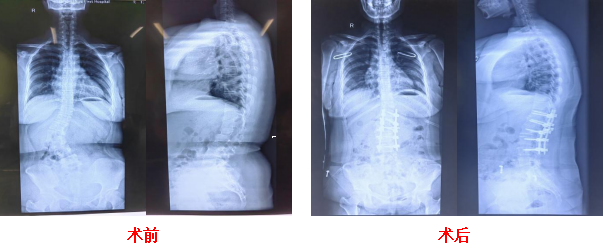

近期半椎体畸形矫正手术

CASE 1